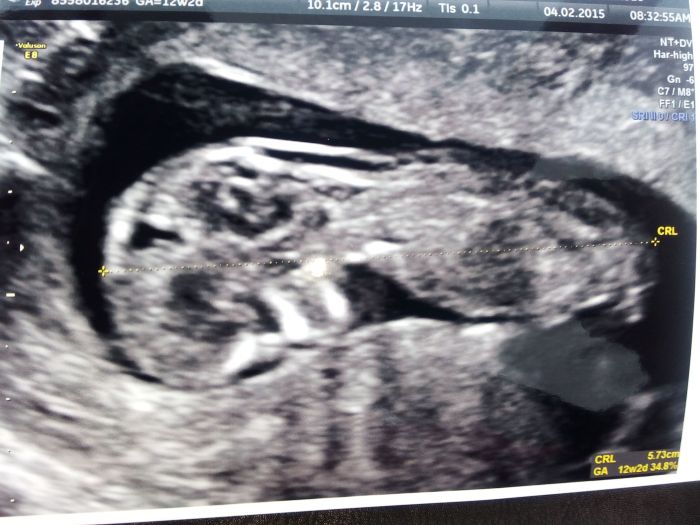

Dobré ráno děvčátka,no tak já mám foteček hodně, nechávám si vytisknout skoro pokaždé co jsem na kontrole :-)přikládám vám fotečky od teď až po mrňouska úplně na začátku těhu :-) založím je asi do alba potom, musím nějaké koupit